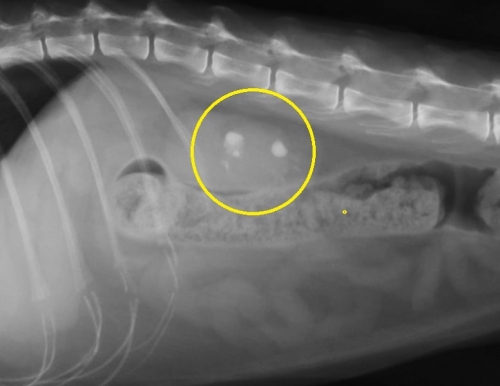

猫でみられた腎結石のレントゲン写真を左下図に示します。その中で「白く見える3つの影」が腎臓(腎盂内)にある腎結石です。イメージしやすいように結石と腎臓の位置関係を右の模式図に重ねてみました。結石は実際には腎臓の腎盂内にあるので外からは見えません。一番左の結石は尿管に落ちかかっています。

下の写真は両側の腎盂内に比較的大きな腎結石が発見された猫の腹部レントゲン写真です。上写真が縦方向下が横方向のものです。

下のレントゲン像の黄色の縁で囲んだ目立たない結石は画像でこそ目立ちませんが、急性の尿管閉塞を生じている尿管結石です。尿管閉塞というのはお腹の中で腎臓から膀胱をつなぐ細い尿管で生じます。尿路閉塞として一般的な膀胱結石による尿道閉塞とその仕組みは同じです。